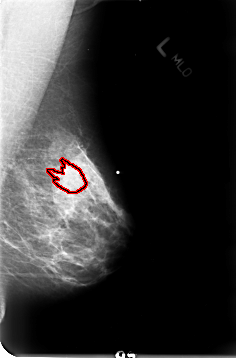

B_3023_1.RIGHT_MLO

RIGHT_MLO LINES 4680 PIXELS_PER_LINE 3064 BITS_PER_PIXEL 12 RESOLUTION 50 NON_OVERLAY

FILE: B_3023_1.LEFT_CC.OVERLAY

TOTAL_ABNORMALITIES 1

ABNORMALITY 1

LESION_TYPE MASS SHAPE IRREGULAR-ARCHITECTURAL_DISTORTION MARGINS OBSCURED-ILL_DEFINED-SPICULATED

ASSESSMENT 4

SUBTLETY 3

PATHOLOGY MALIGNANT

TOTAL_OUTLINES 1

BOUNDARY